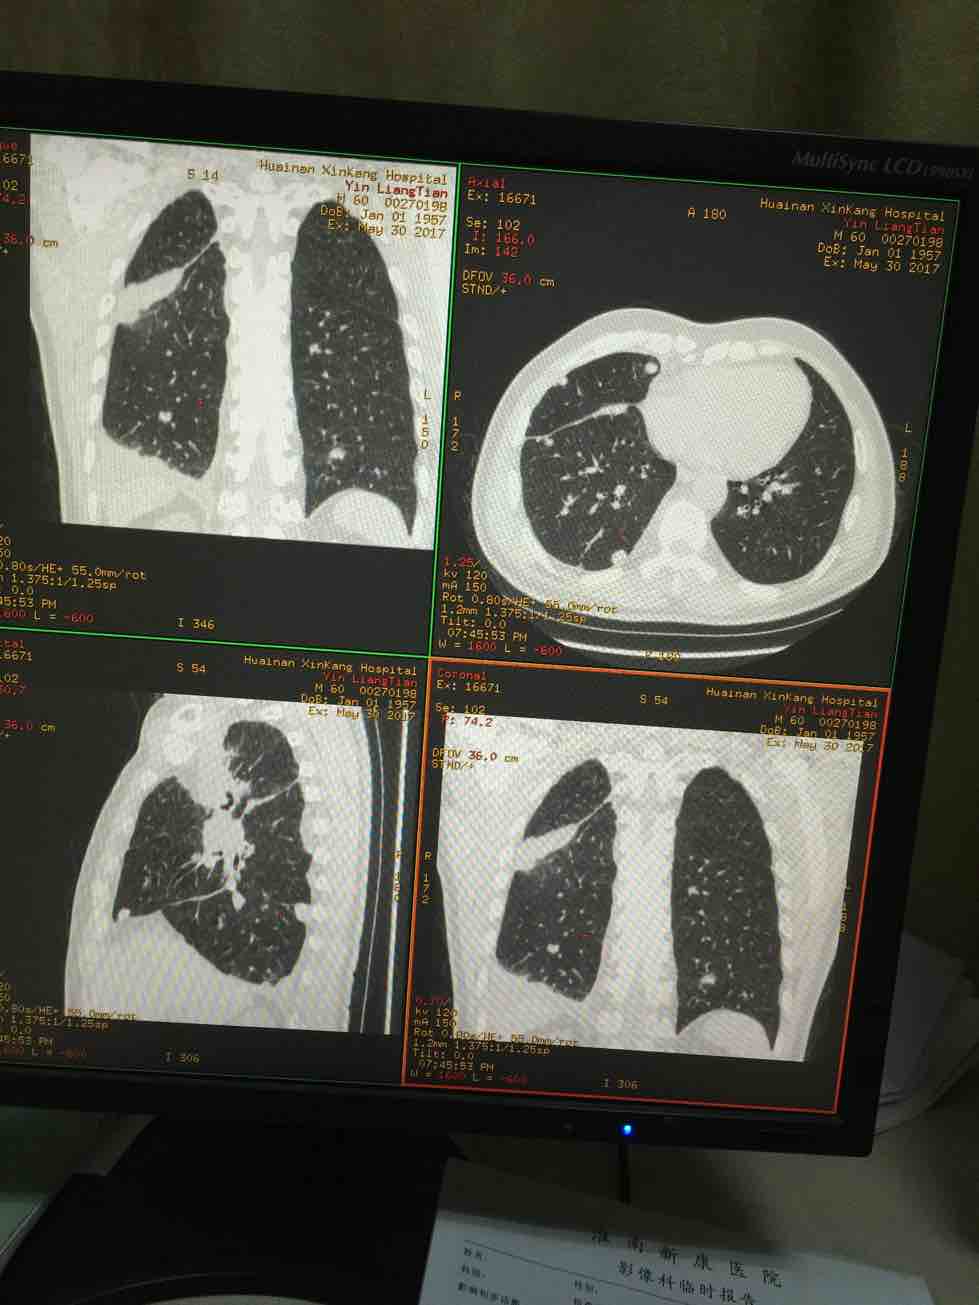

我父亲2016年一月发现右上肺癌晚期,培美曲塞六个疗程后行了右上肺原发灶两周放疗,于去年7月份进展,后来基因检测没有突变,盲吃印版易瑞沙后结果有效,瘤子很快缩小,至今吃了第八盒,最近说胸痛今日CT复查(结果如图)进展了,接下来如何治疗还请各位老师给予指导,谢谢!!